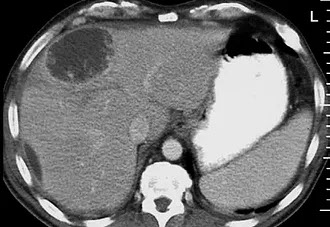

Enfermedad Hepática Poliquistica

La enfermedad poliquística hepática aislada (PCLD) es un trastorno genético que se caracteriza por la aparición de numerosos quistes por todo el hígado y que en la mayoría de los casos se describe como una enfermedad poliquística hepática autosómica dominante (ADPCLD).

Afecta con mayor frecuencia a mujeres que a hombres. Los quistes suelen aparecer después de los 40 años de edad y no son detectables antes. Su número y tamaño se incrementa con la edad. Los síntomas dependen de la masa (efecto de compresión) y pueden incluir distensión abdominal, reflujo gastro-esofágico, saciedad precoz, disnea, disminución de la movilidad y dolor en la espalda por la hepatomegalia. Algunos pacientes están asintomáticos.